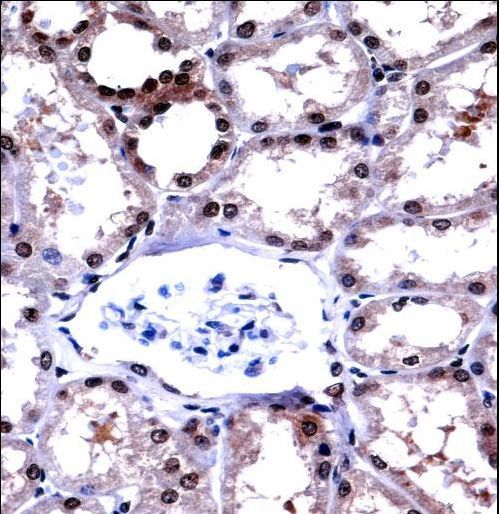

Supportive validation

- Submitted by

- LSBio (provider)

- Main image

- Experimental details

- APLP2 Antibody immunohistochemistry of formalin-fixed and paraffin-embedded human kidney tissue followed by peroxidase-conjugated secondary antibody and DAB staining.